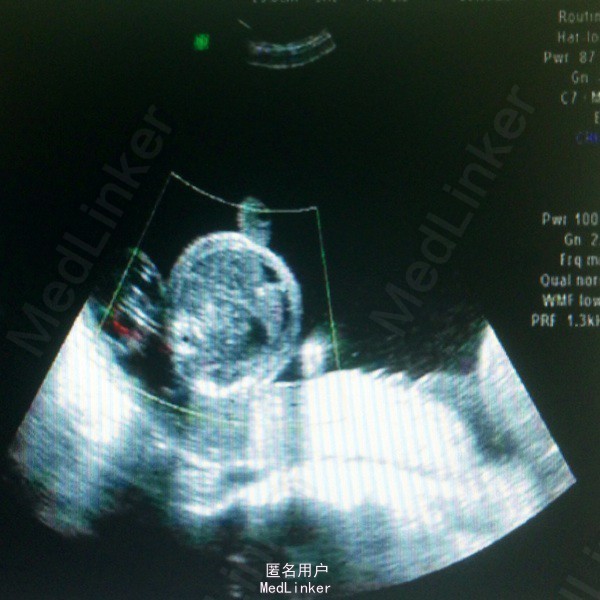

主诉:孕28周3天,彩超示双胎输血综合征 现病史:26岁女性患者,平素月经规律,现孕28周3天,昨日外院查B超提示双活胎,羊水量极多,B胎儿全身皮肤及内脏、脐带水肿,S/D比值偏高,考虑双胎输血综合征可能,今来我院复查B超提示,A胎儿存活,B胎儿停滞发育,A胎儿相当于28周2天,B胎儿相当于29周2天,I级胎盘,羊水多,收入院。

体检:腹隆,肝脾肋下未触及,双下肢水肿+,宫高43cm,腹围112cm,FHR130bpm,未及宫缩,骨盆外测量23-27-19-9 辅助检查:B超结果如现病史中所述,具体见图